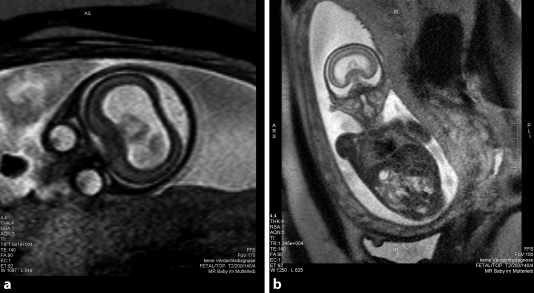

Fetale Magnetresonanztomografie Springerlink